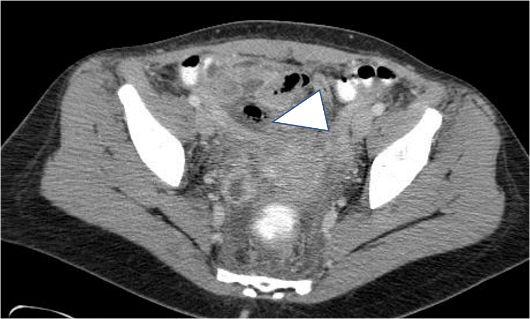

Acute Appendicitis is diagnosed at two stages: the early form (frequent) and the advanced form (complicated, unusual) [8, 63]. We require two criteria in order to make the diagnosis of a simple and acute appendicitis: the visualization of a swollen appendix, with the diameter greater than 6mm, with or without an enhancement of the wall and accompanied by an infiltration of peri-appendicular fat or the identification of an appendicolith associated with an infiltration of the pericaecal fat (Figure 7) [60-65]. Secondary and non-specific anomalies of appendicitis are the presence of an appendicolith, the absence of contrast medium in the appendiceal lumen, extra-digestive gas, a fluid collection or lymph nodes, a localized thickening of the caecal walls [52-54, 60-62] (Figure 8). The thickening of the wall of the cecum can take on a very localized appearance, resulting in an arrow-like structure of the cecal contrast, opposite the entrance of the inflamed appendix ("cecal arrowhead sign") [62]. This sign, related to appendicitis, is associated with a high specificity 100% and a sensitivity of 30%.

Figure 8: Appendicitis not seen in US and clearly identified at CT. (A) US focused on the right iliac fossa: infiltration of pelvic fat and gazeous structures with a linear arrangement (arrows). (B) and (C) CT shows an enlarged and inflamed appendix (arrowhead), appendicolitis (arrow) and infiltration of periappendiceal fat.